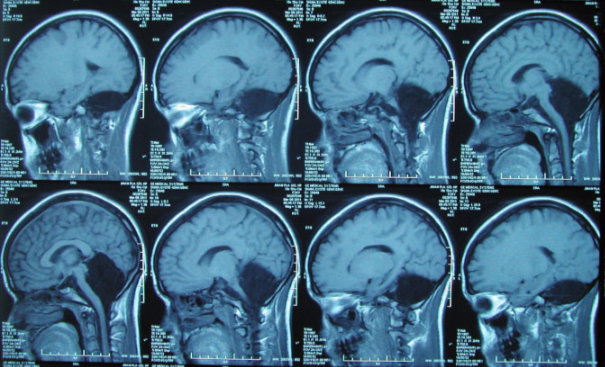

Se trata de una estructura del sistema nervioso central que se sitúa en la parte posterior del encéfalo, por debajo del cerebro y detrás del tronco encefálico. A pesar de su tamaño relativamente pequeño contiene casi la mitad de las neuronas del cerebro, lo que subraya su complejidad e importancia (García et al., 2009).

Con relación a lo anatómico, consta de tres lóbulos a cada lado de sus dos hemisferios conectados por el vermis. Entre ellos se encuentra el lóbulo anterior, que se aprecia en la cara superior de cerebelo; el posterior, situado entre los surcos primario y posterolateral; y el floculonodular, que corresponde a la parte inferior de la cara anterior.

Asimismo, la paciente estaba casada y tuvo a su hija con un embarazo y parto sin complicaciones. No obstante, tras los análisis de tomografía computarizada, los resultados demostraron ausencia de tejido cerebeloso (Yu et al., 2015).